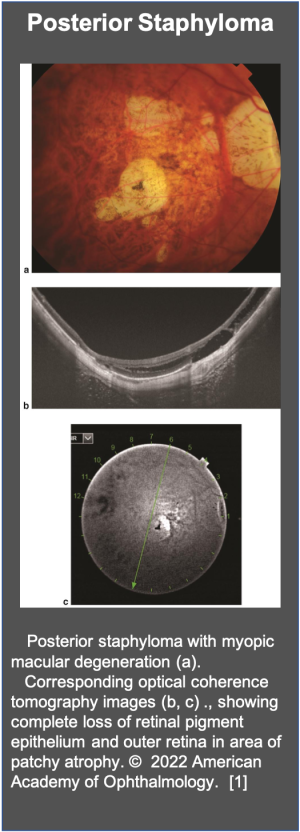

- ↑ American Academy of Ophthalmology. Posterior staphyloma. https://www.aao.org/image/posterior-staphyloma-2. Accessed May 31, 2022.

Diagnosis is made clinically through direct observation, via the indirect ophthalmoscope. It is accompanied by an optical coherence tomography (OCT), which allows clinicians to examine the curvature and scope of the staphyloma. Recent advances in OCT have enabled clinicians to observe the fundus in more detail. Researchers in Japan recommend using swept-source OCT, which can obtain images of deeper tissues, such as the choroid, sclera, and optic nerve, to capture staphylomas that are often missed by current technology. OCT is very important to rule out myopic maculopathy or myopic traction maculopathy in such cases.